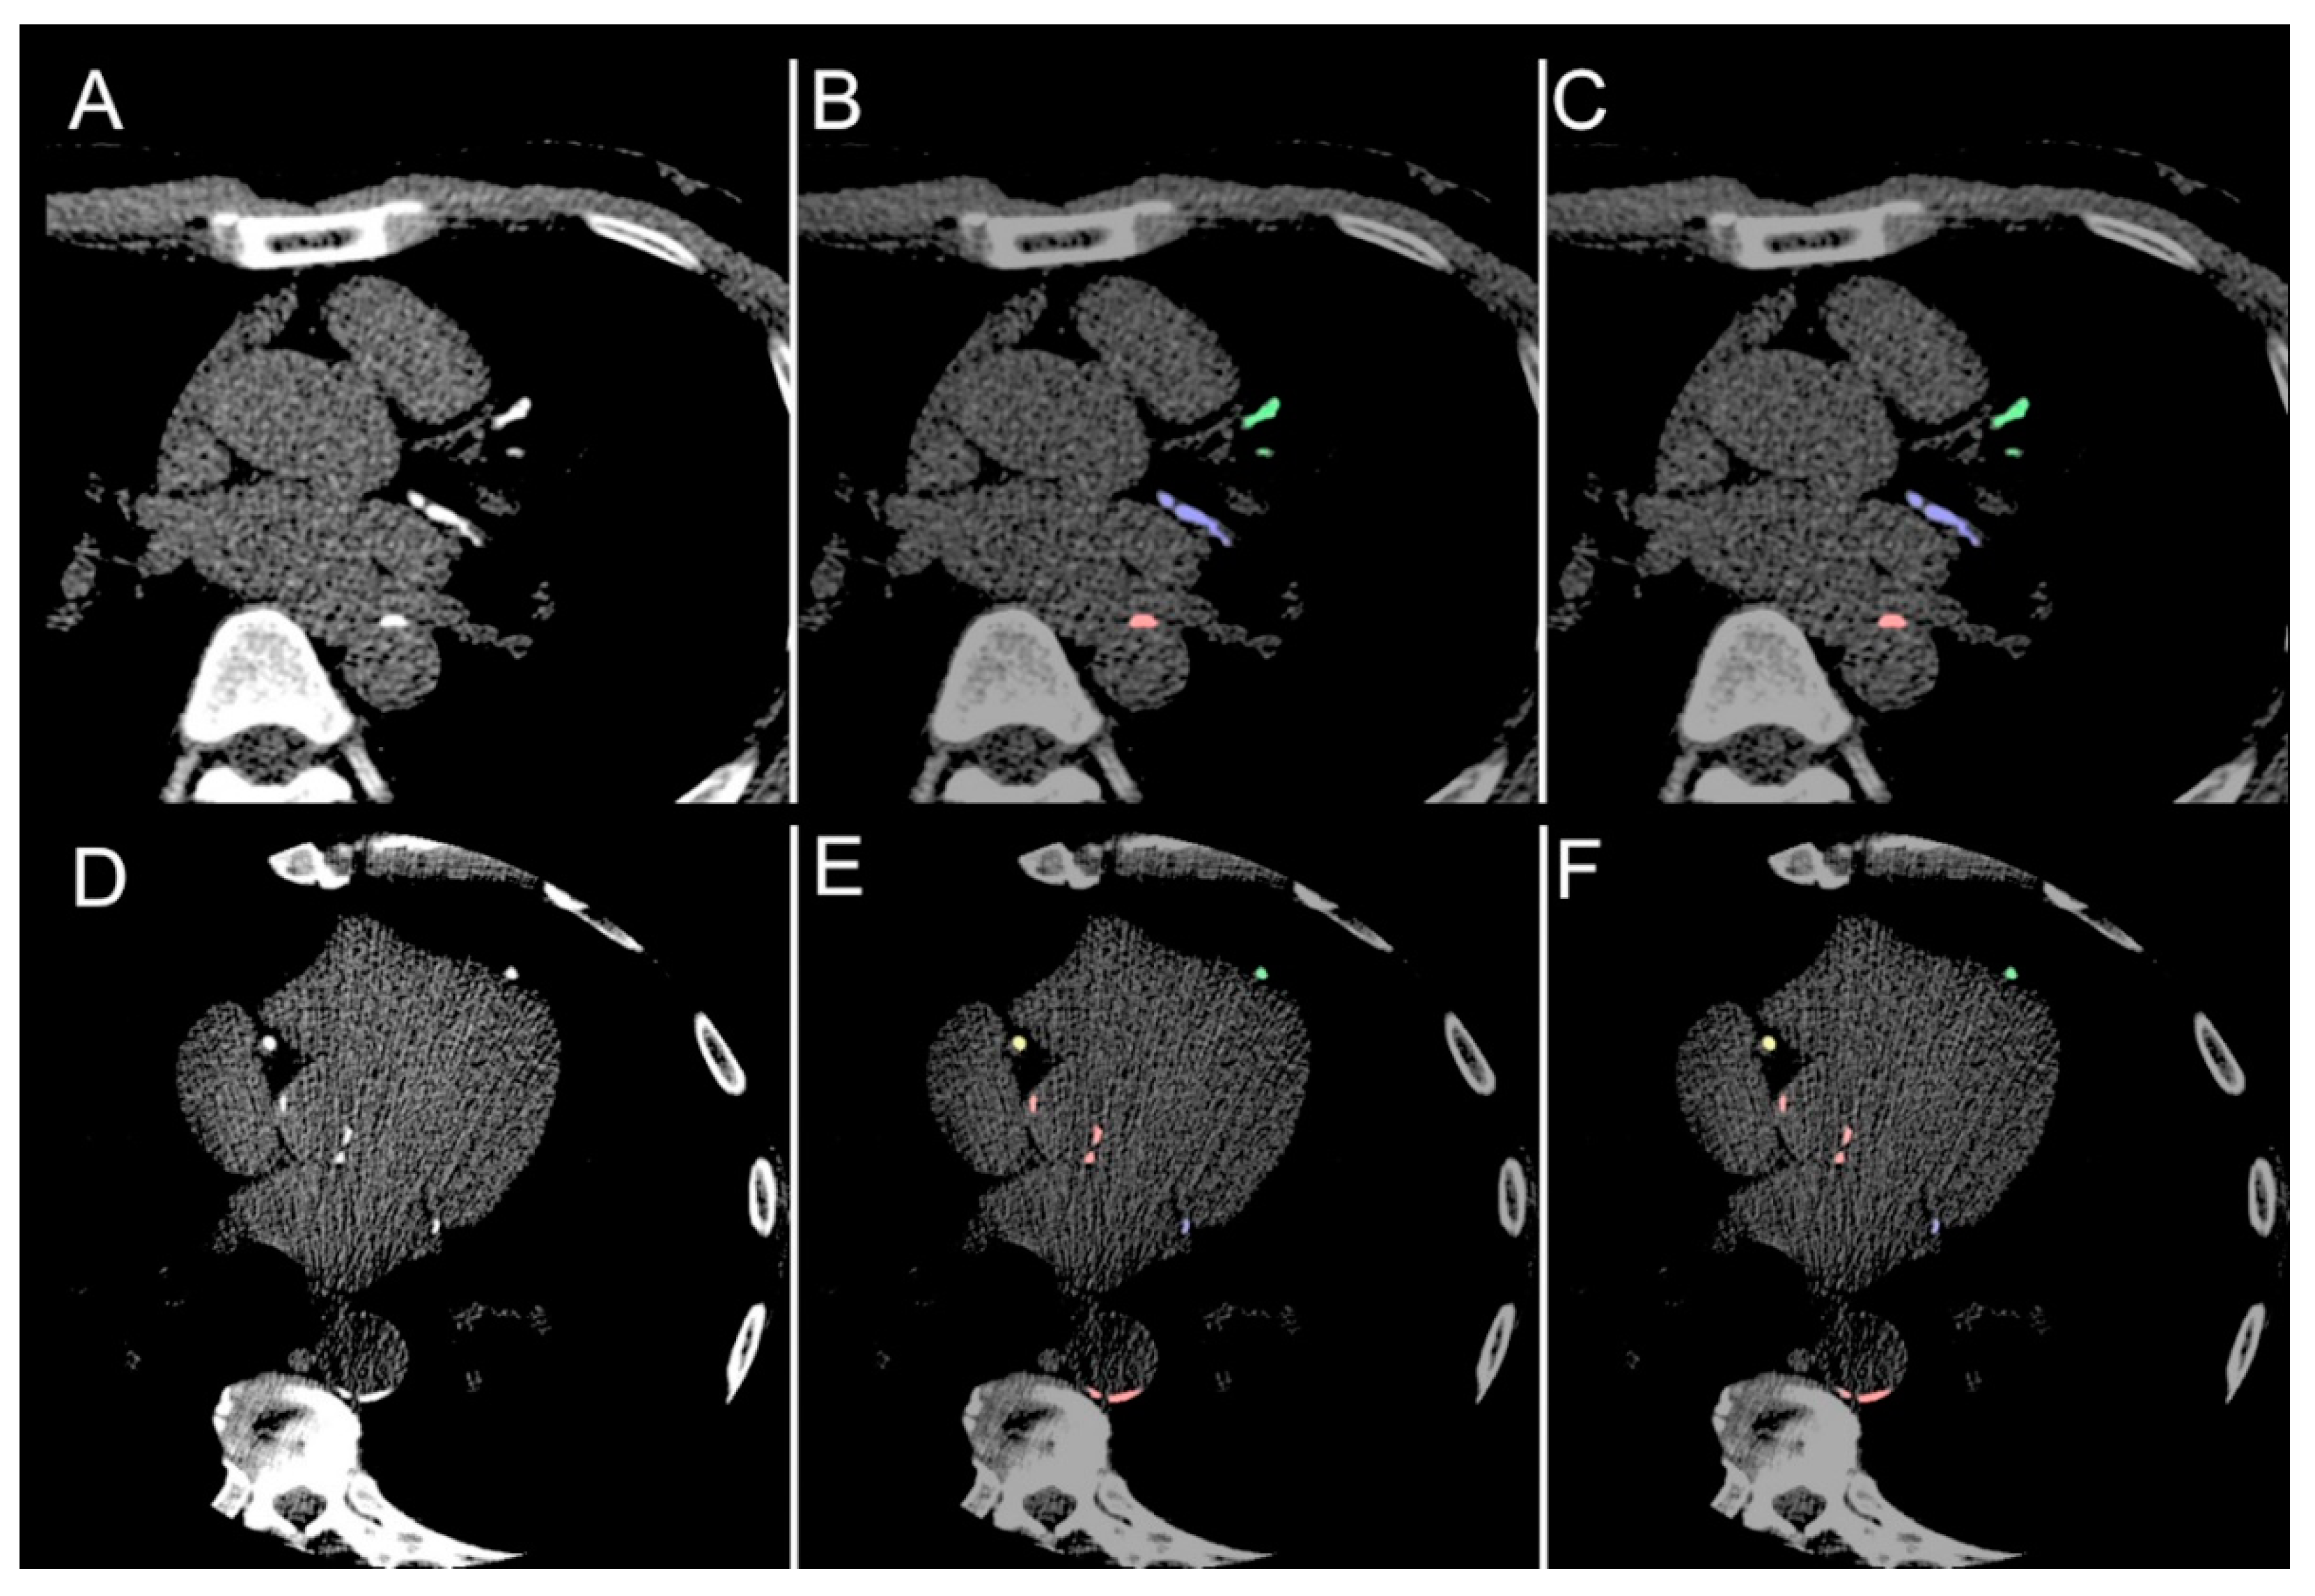

| Structure | Category | Dice Score | ||

|---|---|---|---|---|

| Median | Quartile (1st, 3rd) | p | ||

| Total coronary (LAD + RCA + LCx) | Overall | 0.952 | (0.921, 0.981) | - |

| LAD | Overall | 0.971 | (0.930, 1.000) | - |

| Male | 0.963 | (0.919, 1.000) | 0.058 | |

| Female | 0.988 | (0.968, 1.000) | ||

| Age < 65 years | 0.970 | (0.941, 0.999) | 0.980 | |

| Age ≥ 65 years | 0.975 | (0.911, 1.000) | ||

| RCA | Overall | 0.963 | (0.889, 0.991) | - |

| Male | 0.951 | (0.880, 1.000) | 0.633 | |

| Female | 0.977 | (0.923, 0.991) | ||

| Age < 65 years | 0.964 | (0.874, 0.999) | 0.875 | |

| Age ≥ 65 years | 0.959 | (0.899, 0.987) | ||

| LCx | Overall | 0.955 | (0.894, 1.000) | - |

| Male | 0.954 | (0.887, 1.000) | 0.388 | |

| Female | 0.958 | (0.942, 0.998) | ||

| Age < 65 years | 0.954 | (0.905, 0.999) | 0.897 | |

| Age ≥ 65 years | 0.955 | (0.887, 1.000) | ||

| Aortic | Overall | 0.832 | (0.759, 0.897) | |

| Male | 0.802 | (0.760, 0.905) | 0.996 | |

| Female | 0.834 | (0.764, 0.883) | ||

| Age < 65 years | 0.833 | (0.776, 0.933) | 0.204 | |

| Age ≥ 65 years | 0.793 | (0.756, 0.862) | ||